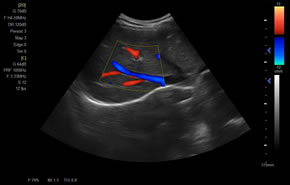

> 彩色血流量圖(CDE)

> 彩色血流分辨增強技術(shù)